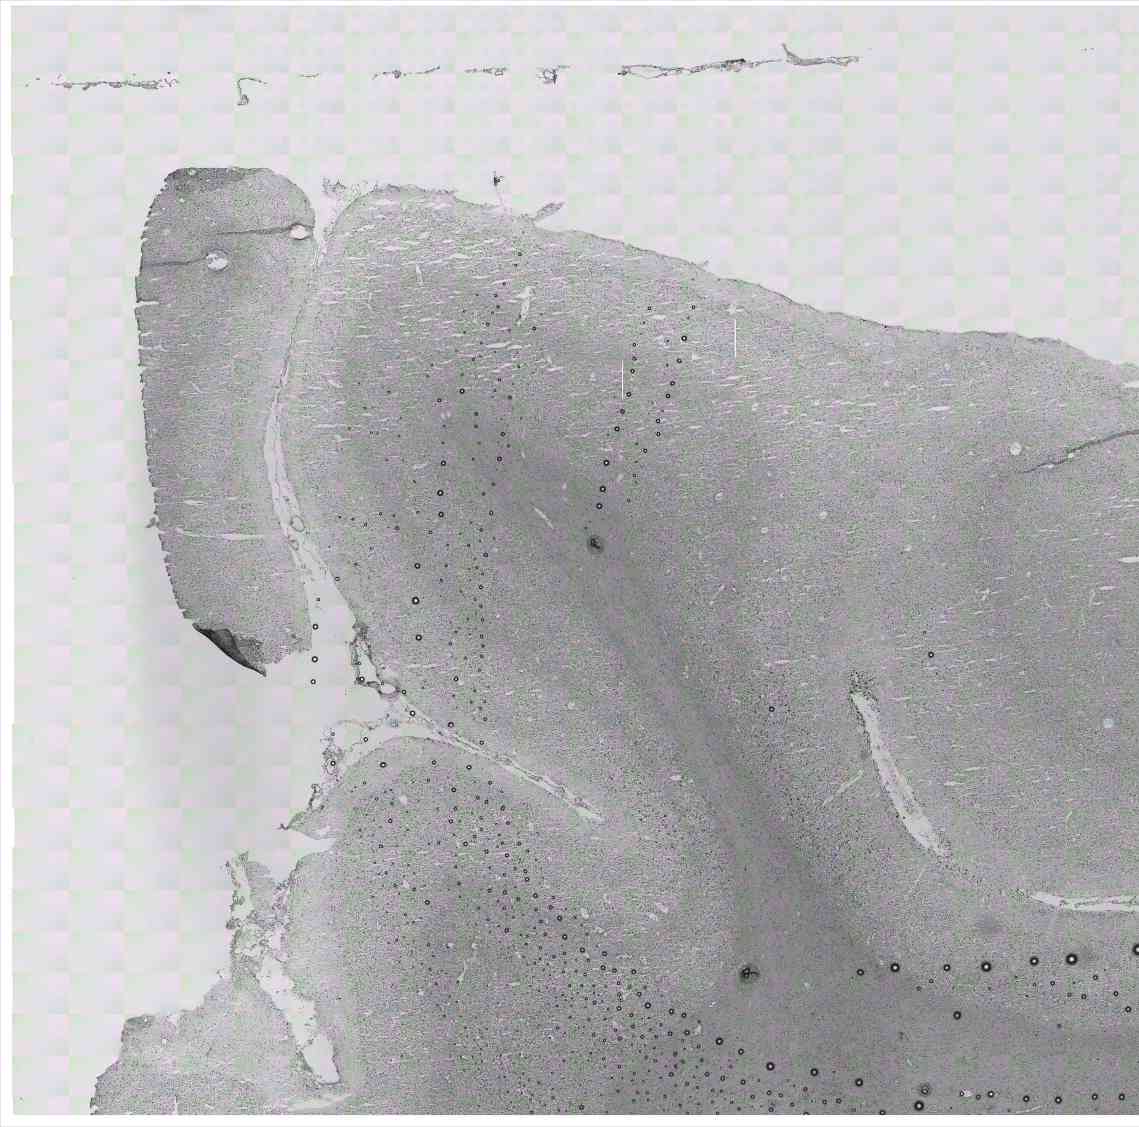

Chip 053 Well C1